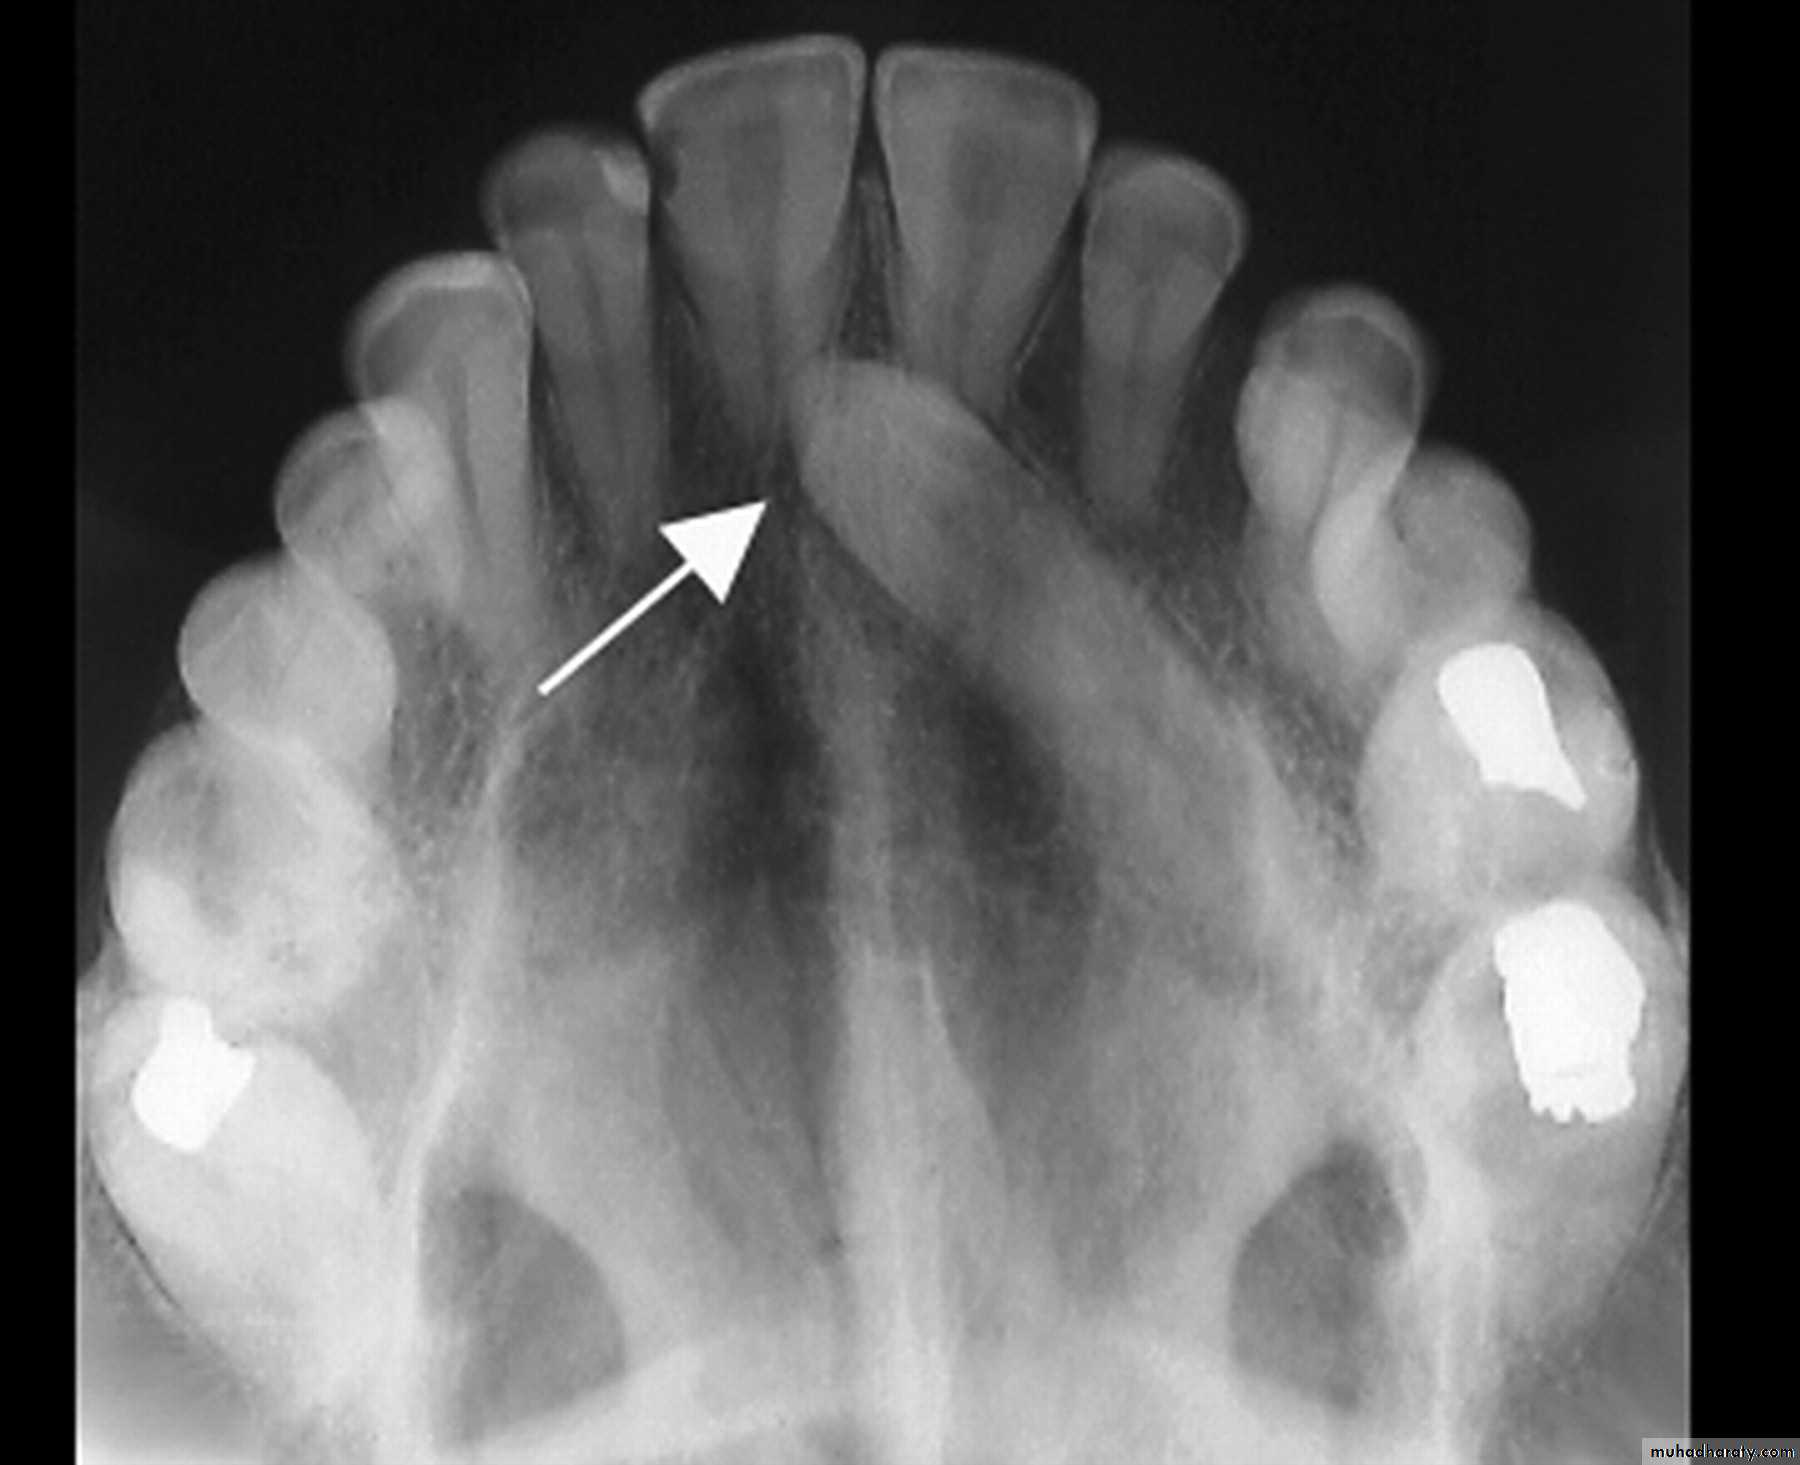

The principle of parallax can be used to determine the position of an unerupted tooth relative to its neighbours. To use parallax two radiographs are required with a change in the position of the X-ray tube between them. The object furthest away from the X-ray beam will appear to move in the same direction as the tube shift. Therefore, if the canine is more palatally positioned than the incisor roots it will move with the tube shift ( Fig. 14.6 b). Conversely, if it is buccal it will move in the opposite direction to the tube shift. Examples of combinations of radiographs which can be used for parallax include two periapical radiographs (horizontal parallax)

This view is useful for assessing the prognosis of a retained deciduous canine and for detecting resorption ( Fig. 14.6 b).•Occlusal view x- ray.